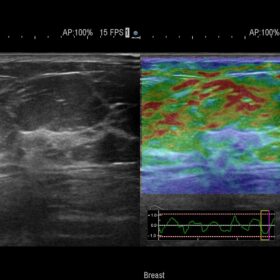

Ultrasound ARIETTA V60 – Image Gallery and Videos

Radiology 2D, Color, Contrast and Elasto mode

- Real-time Tissue Elastography (RTE)visualizes relative tissue stiffness, offering complementary information for diagnosis. It has proven clinical value across a wide breadth of applications including breast, thyroid, liver, and prostate.